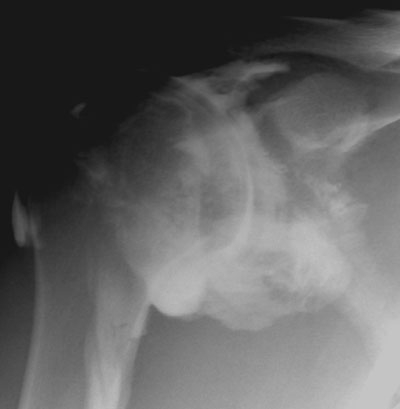

Epaule

Arthrographie de l'épaule

Capsulite rétractile arthrographie (images 1 et 2)

Arthroscanner correspondant (images 3 et 4)